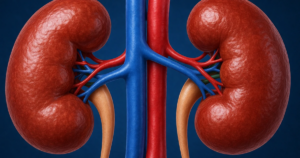

Tiểu đường: 4 sai lầm ăn uống khiến thận tổn thương nhanh hơn

Nắng nóng, thận dễ tổn thương: Bác sĩ chỉ điều quan trọng nhất cần làm

Người tiểu đường nên kiểm tra thận bao lâu một lần?